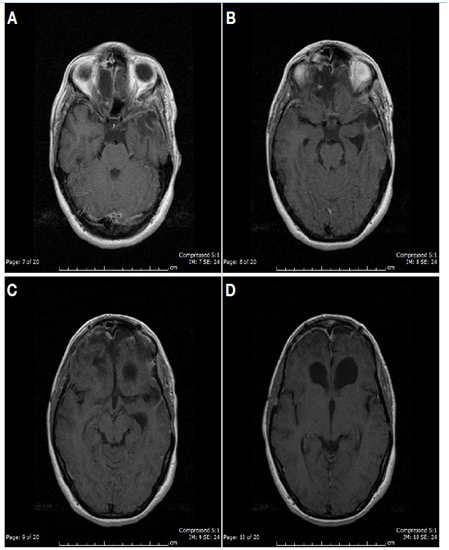

After one year, the patient is reached and a cerebral MRI is performed, which showed a total resection of her two giant meningiomas, without recurrence (Figures 4&5). Neck lesions in situ. The patient refused cervical surgery knowing the possible risks of her decision.

Figure 4 (A,B,C) Postoperative T1 Gadoline enhanced coronal and sagittal MRI shows complete resection of olfatory grove meningioma and left sphenoidal meningioma. White arrows show the place where the tumors were previous to surgical resection.

Figure 5 (A-D) Postoperative T1 Gadoline enhanced axial MRI shows complete resection of both large meningiomas and no ischemic sequelae.